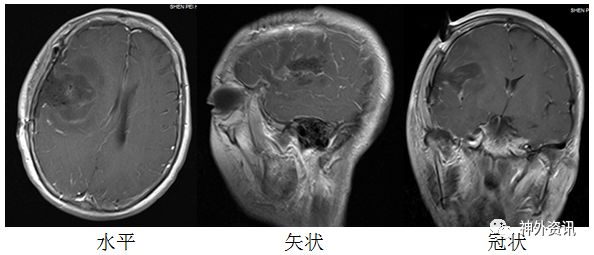

图1.头部MRI增强右侧额叶可见一片状不规则肿块; T1WI上为稍低信号,T2WI上为略高但混杂信号,有不均匀明显强化,约2.8cm×4.3cm×1.9cm。伴有周围水肿。有轻度占位效应。灌注成像:强化肿块区CBF、CBV增高。磁共振波谱:额病灶及周围NAA峰下降,Cho峰升高,伴有脂质乳酸峰出现,提示肿瘤性病变。

术后常规病理报告:(右额颞)胶质母细胞瘤,IDH野生型,WHO IV 级(图5)。

图5. 石蜡切片HE染色,提示胶质母细胞瘤。

免疫组化结果:PTEN +,GFAP +,Ki-67 30%,NF -,NSE +,P53 散在+,MGMT +,Olig2 散在+,ATRX +,BRAF-V600E -,H3K27M -,IDH1 -,S-100 -。